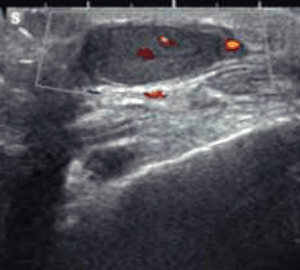

Paciente masculino de 38 años, sin antecedentes, consulta por dolor y edema en muñeca derecha.